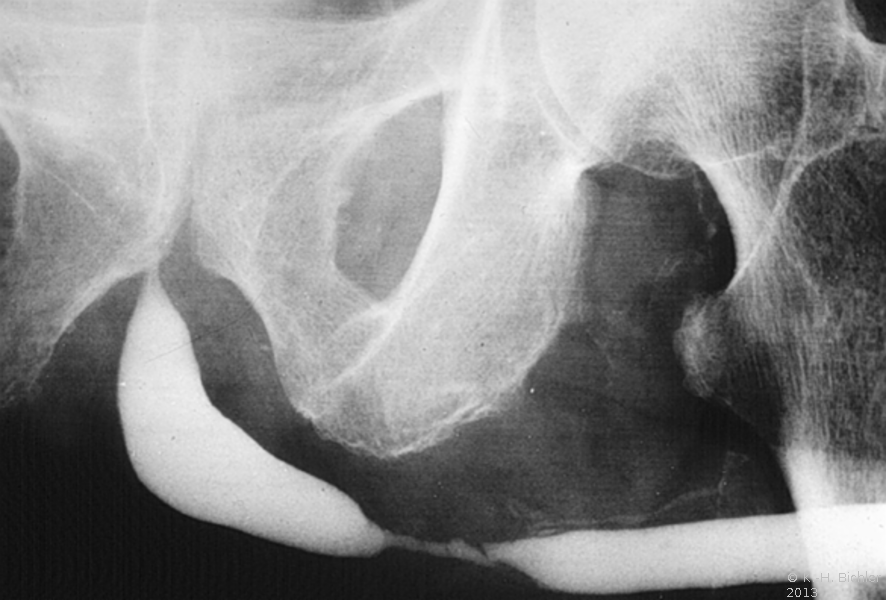

Nach Füllung der Blase mit einem Kontrastmittel, immer mittels Katheter (z.B. via suprapubischen Katheter) wird die normale Miktion unter Röntgendurchleuchtung beobachtet. Damit ist auch eine funktionelle Aussage möglich, ebenso werden pathologische Strukturen im Bereich der Urethra erkannt.

Für die Diagnostik eines vesikoureteralen bzw. -renalen Refluxes ist ebenfalls das MCU erforderlich. Es kann röntgenologisch nach Kontrastmittelfüllung der Harnblase oder nuklearmedizinisch mit radioaktivem Kontrastmittel erfolgen (Abbildung HG1).